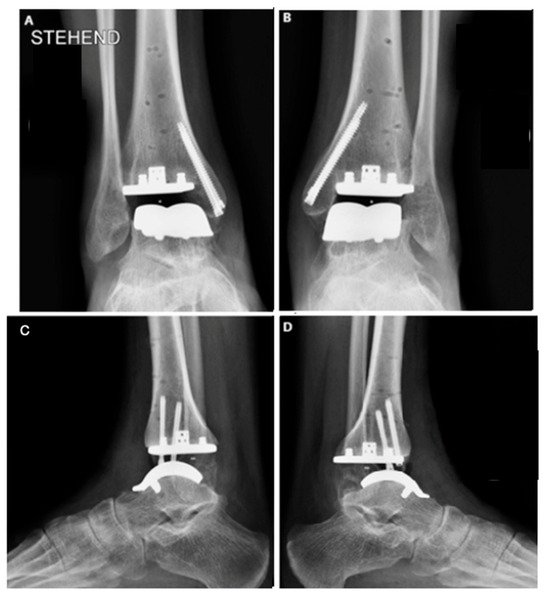

The procedure began with prophylactic percutaneous fixation of the medial malleolus using two cannulated screws. This approach was selected based on imaging studies revealed subchondral cysts in the region, which, together with the osteopenia commonly seen in hemophilic patients, could predispose to fractures. The fixation aimed to prevent intraoperative and postoperative fracture of the medial malleolus.

Once the guides were positioned, fluoroscopy was used to verify the correct alignment of the cuts (Figure 4). Adjustments regarding rotation, varus, valgus, slope, and the amount of bone to be resected were made as necessary. A 5 mm bone resection is typically recommended when using a mobile system; however, in this case, due to the patient’s underlying osteopenia, a more conservative resection was performed.

Imaging studies also show that the implant is well positioned, with no detectable loosening or movement, and has good ankle alignment. Further follow-up visits are necessary for long-term evaluation.

Figure 4. Bilateral total ankle arthroplasty in the hemophiliac patient two weeks after the surgery. VANTAGE Total Ankle Arthroplasty mobile-bearing system with 2 prophylactic screws in medial malleolus in AP and side view, right ankle (A,C), and left ankle (B,D).